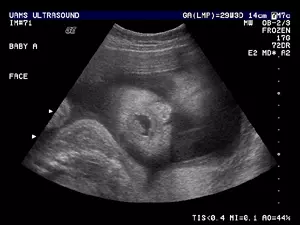

V naši ambulanti se predvsem trudimo, da bi imeli čimbolj profesionalen, diskreten in strokoven pristop k problematiki, ki jo obravnavamo. Da pa bi našim pacientkam zagotovili le najboljše, se nenehno izobražujemo in skušamo dosledno slediti sodobnim smernicam, ki se izoblikujejo tako pri nas kot tudi v tujini. Zato je med drugim na voljo tudi 3d 4D UZ - oziroma ultrazvočni pregled ploda.

V sklopu svoje ambulante ponujamo ginekološko in porodniško dejavnost, poleg tega svojim pacientkam nudimo preglede dojk in različne oblike ultrazvoka. Samoplačniško izdelamo tudi 3D 4D UZ.